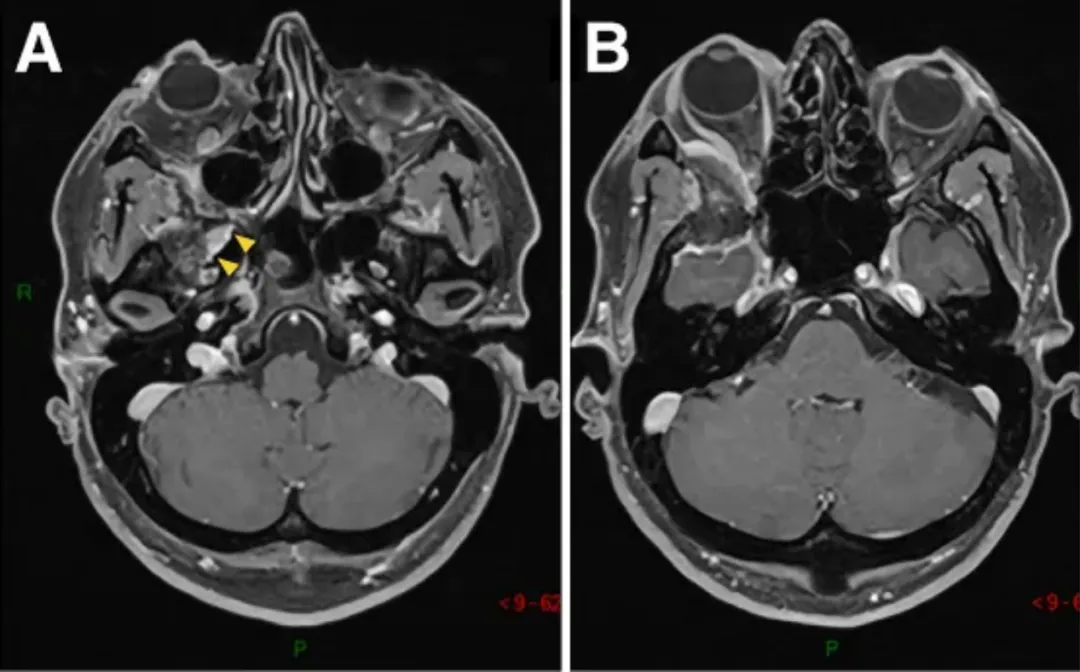

圖1A-D:術(shù)前MR顯示蝶眶區(qū)腫瘤占位,增強(qiáng)均勻病灶,浸潤(rùn)延伸至翼腭窩(黃色箭頭)。

E-H:術(shù)后軸位MR圖像顯示腫瘤完全切除。